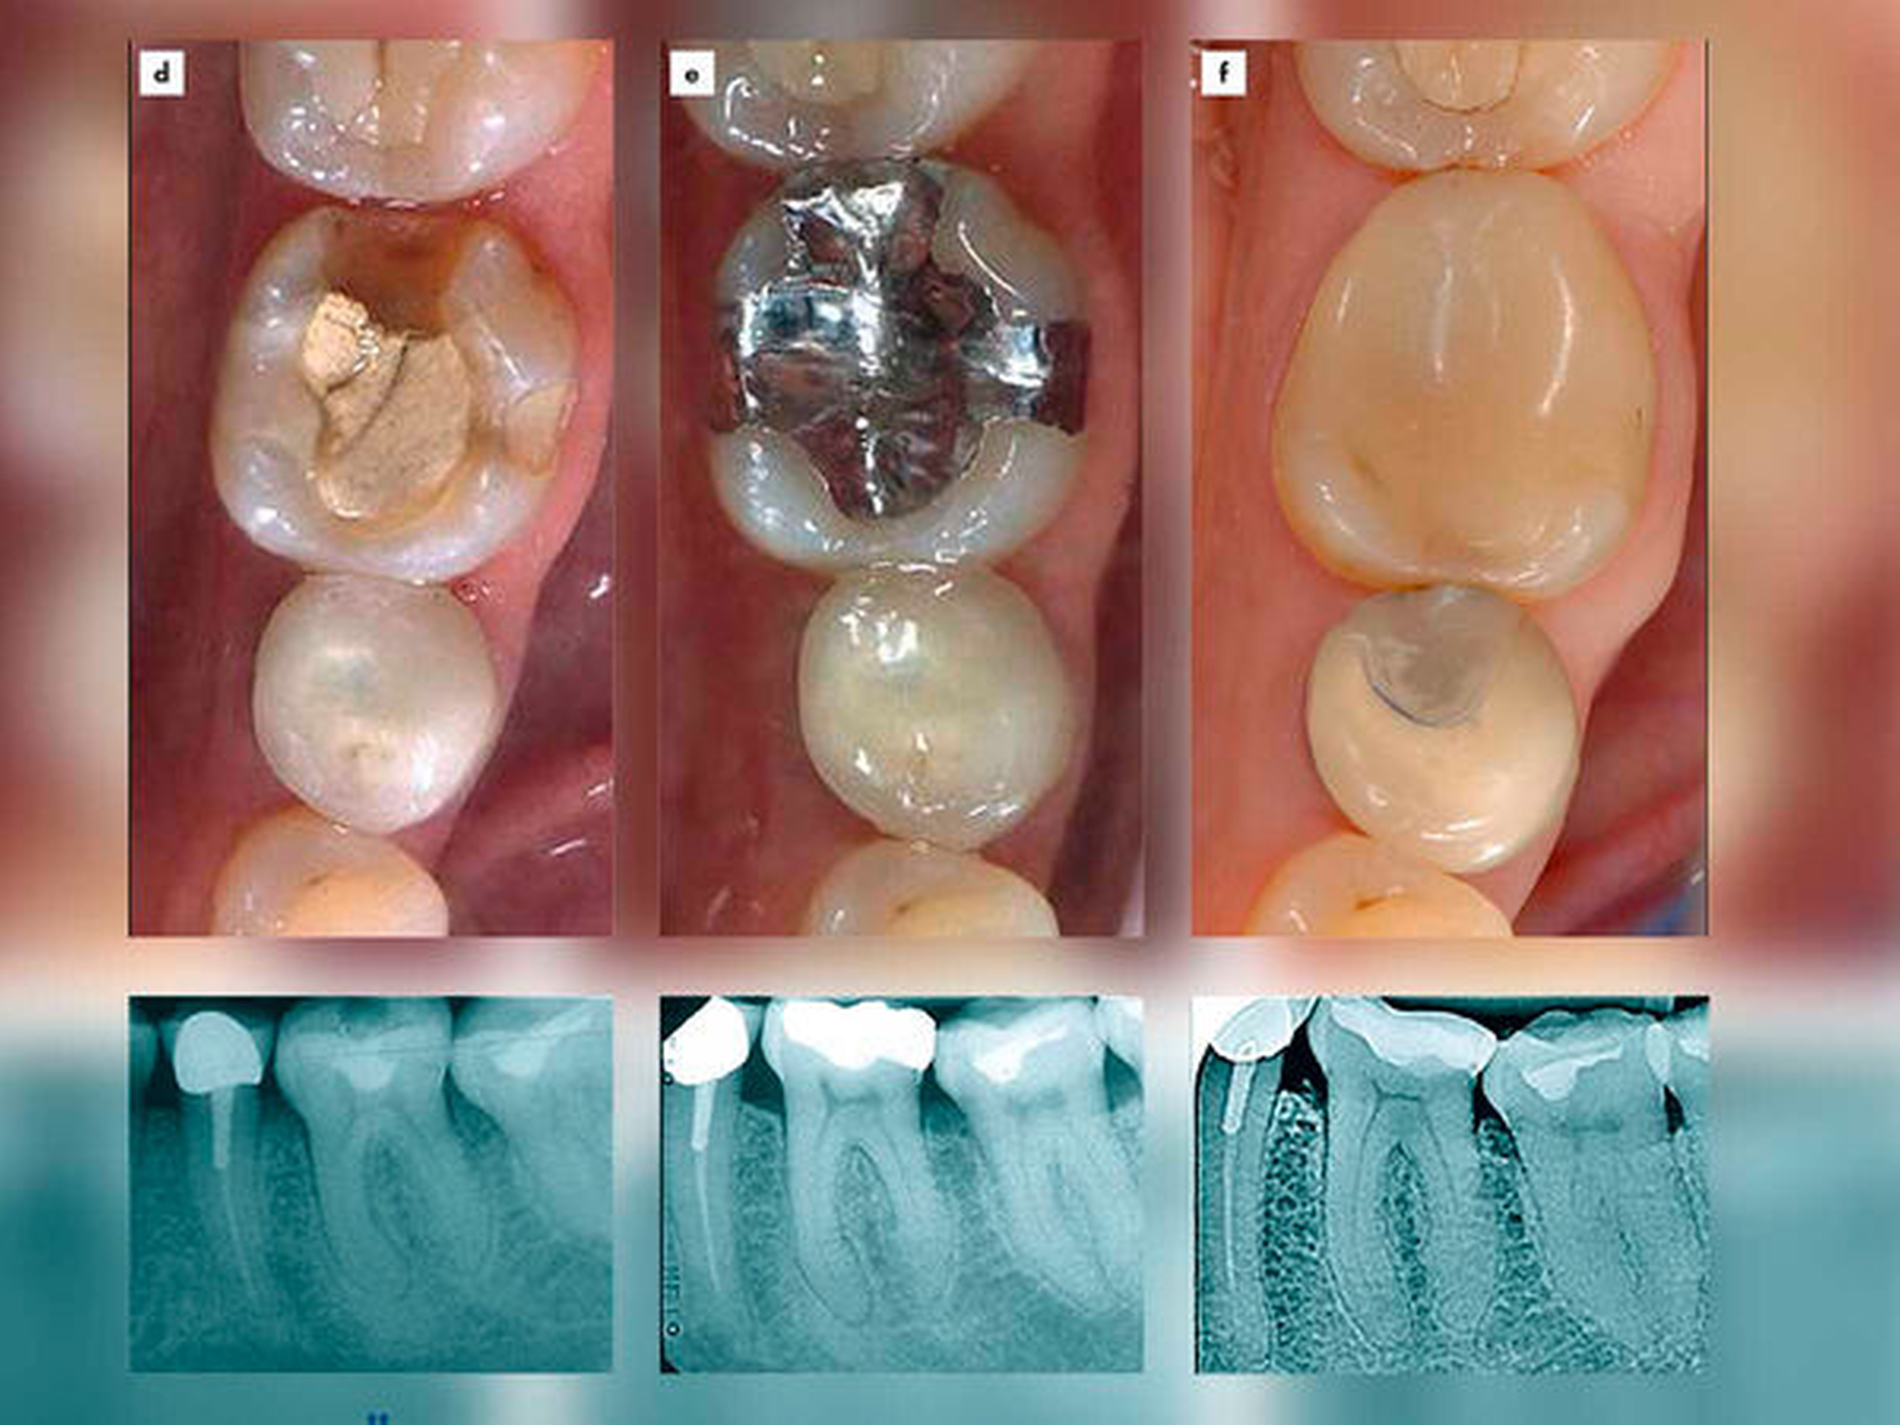

Im Folgenden wird das Vorgehen anhand der Behandlung und Betreuung einer 48-jährigen Patientin beschrieben (Abbildung 2): Die anfangs gesunde Frau war seit Jahrzehnten mit Amalgamrestaurationen versorgt, die sie ohne Einschränkungen tolerierte. Dennoch ließ sie sich sämtliche intakten Restaurationen entfernen und durch Keramik-Inlays sowie VMK-Kronen ersetzen, da ihr dies von einem alternativmedizinisch orientierten Behandler aus Gründen des „vorbeugenden Gesundheitsschutzes“ angeraten worden war.

Aus ungeklärter Ursache traten unter anderem am Zahn 36 Schmerzen im Sinne postoperativer Sensibilitäten auf, so dass dort schließlich nur noch diverse instabile provisorische Restaurationsmaterialien zum Einsatz kamen. Der Patientin war auf der Grundlage fragwürdiger Testmethoden vermittelt worden, sie leide unter einer „Unverträglichkeit“ gegenüber allen gängigen zahnärztlichen Restaurationsmaterialien einschließlich Komposit-Kunststoffen. Bei der Vorstellung in der Poliklinik für Zahnerhaltungskunde der MZK-Klinik des Universitätsklinikums Heidelberg zeigten sich abgesehen von der insuffizienten Versorgung des Zahnes 36 weder klinisch noch röntgenografisch weiterreichende pathologische Befunde. Die parodontalen Sondierungstiefen waren leicht erhöht und es kam generalisiert zum Bluten nach Sondieren im Sinne einer parodontalen Entzündung. Die Patientin legte bei der Vorstellung in der Klinik den Therapievorschlag eines weiteren alternativmedizinisch orientierten Kollegen vor, den dieser auf der Grundlage „bioenergetischer“ Testungen (hier: „Resonanzketten“) erstellt hatte. Danach sollten zwei erhaltungswürdige Zähne wegen angeblich negativer energetischer Einflussnahmen auf die Bauchspeicheldrüse und den Enddarm der Patientin extrahiert werden (Abbildungen 2a bis 2c). Die Patientin stand mittlerweile alternativmedizinischen Vorstellungen sehr vertrauensvoll gegenüber und machte sich die Sicht des Alternativmediziners im Sinne einer malignen Arzt-Patient-Beziehung zu eigen. Sie verlangte nachdrücklich die Extraktion der beiden Zähne 35 und 36 und bat um die Suche von Dentalmaterialien, die sie tolerieren könne.

In der Klinik wurde ihr eröffnet, dass es sich bei den „bioenergetischen“ Tests des alternativmedizinisch orientierten Kollegen um umstrittene Methoden handelt. Nach einer umfassenden zahnärztlichen Untersuchung wurde ihr angeboten, zunächst die parodontalen Entzündungsreaktionen anzugehen, worauf sie – wenn auch zunächst sehr misstrauisch und widerstrebend – einging. Nach professionellen Zahnreinigungen in Verbindung mit einem Mundhygienetraining, das sich insbesondere auf den sachgerechten Einsatz von Interdentalraumbürsten bezog, kam es rasch zu einem von der Patientin positiv registrierten Rückgang des Zahnfleischblutens. Der Sinn dieser nicht-invasiven vorbereitenden Maßnahmen lag nicht nur in der Behandlung der parodontalen Entzündung. Sie verfolgten darüber hinaus Zweck, ein persönliches Vertrauensverhältnis aufzubauen. Es gelang nach und nach, die Patientin von dem Extraktionswunsch abzubringen. Aufgrund ihrer nahezu unerschütterlichen Vorstellung einer „Kunststoffunverträglichkeit“ kam ein Einsatz von Kompositen zunächst nicht in Betracht. Sie stimmte jedoch einer erneuten Versorgung mit Amalgam zu, das sie nachweislich über mehrere Jahrzehnte sehr gut vertragen hatte. Die Eingliederung der Amalgamrestauration führte zur sofortigen und anhaltenden Beschwerdefreiheit (Abbildungen 2d und 2e).

Bei der Patientin wurde das zahnerhaltende Konzept, nämlich präventive Maßnahmen möglichst offensiv, chirurgische und restaurative Eingriffe hingegen möglichst defensiv anzugehen, erfolgreich umgesetzt. Die Zähne sind nach einer Beobachtungsdauer von nunmehr 28 Jahren noch in situ (Abbildung 2f). Die inzwischen 76-jährige Patientin erscheint regelmäßig zum Recall. Allgemeinmedizinisch ist sie gesund, es bestehen keine Hinweise auf eine Erkrankung der Bauchspeicheldrüsen oder des Enddarms. Nach einer sukzessiven Verfestigung des Vertrauensverhältnisses konnten inzwischen bei der zahnärztlichen Versorgung auch die von der Patientin aufgrund der alternativmedizinisch verursachten Noceboeffekte anfangs abgewehrten Kompositkunststoffe ohne jegliche negative Reaktionen zum Einsatz kommen.